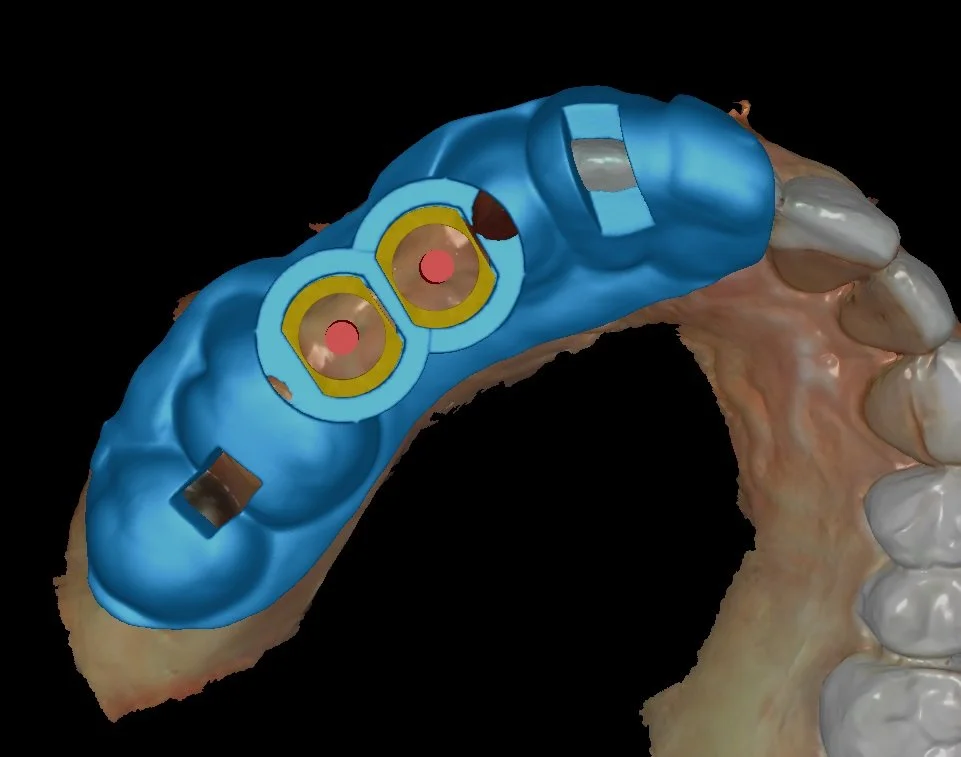

Using specialized software, the CBCT and intraoral scans were merged into a single digital model. The missing teeth were digitally designed in their ideal position, and two high-quality implants were carefully planned according to the final crowns and available bone — without the need for bone grafting.

A customized digital surgical guide was then designed and 3D-printed using FDA-approved material to ensure exact implant placement during surgery.